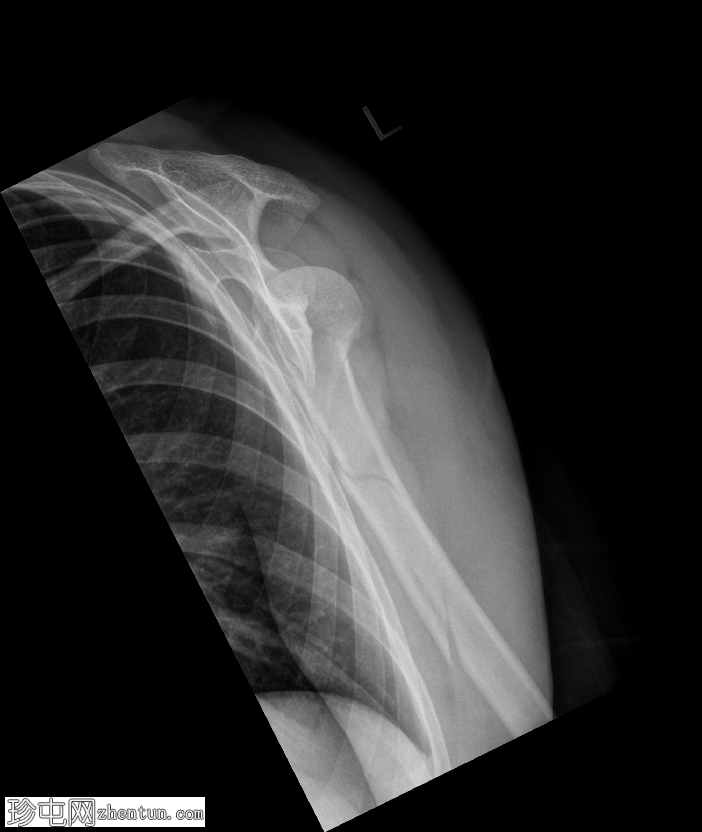

正位

肱骨近端粉碎性移位骨折,累及骨干近端半部、外科颈,并延伸至大结节。

肱骨头在肩关节内向下半脱位,肩峰肱骨间距增大。